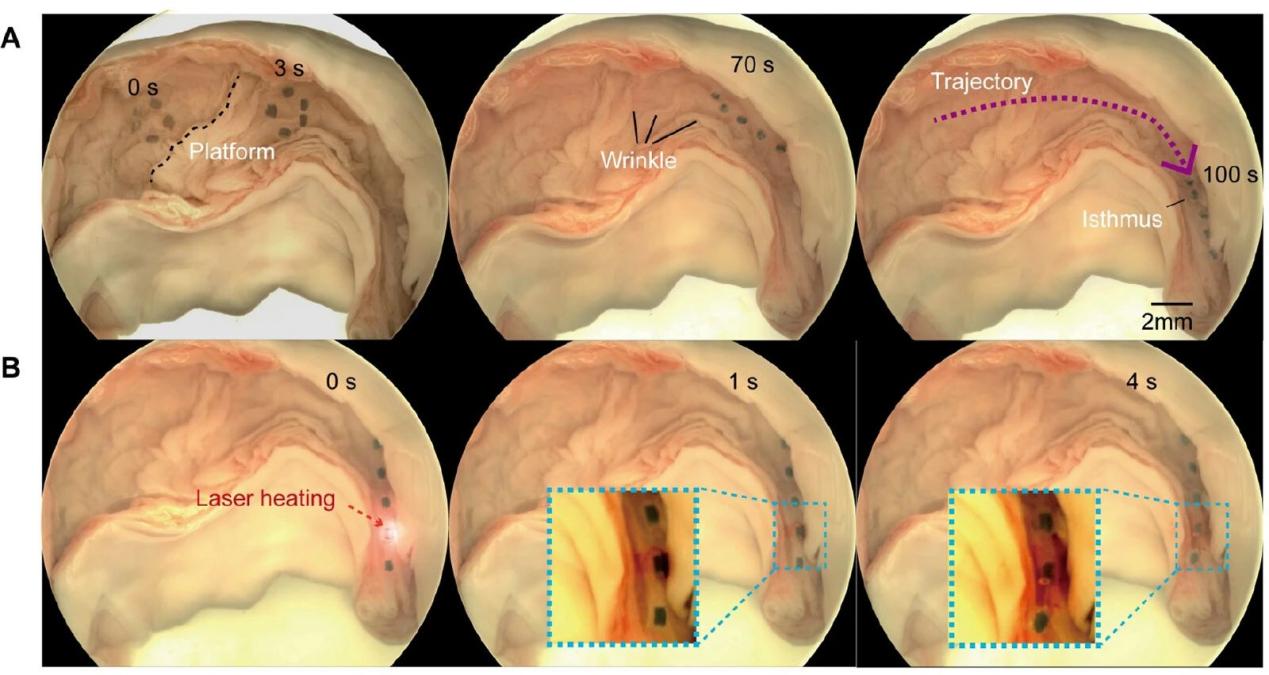

通过在离体猪输卵管中控制微型软体机器人执行自适应多模态运动和药物递送,以证明微型机器人在真实小腔道中的适用性。离体输卵管提供了真实的生理环境,具有各种类型的屏障,包括平坦区域、皱纹、粘液层和狭窄通道。

在磁场下,微型机器人朝着目标区域前进,在100秒内运动了55mm,在目标区域快速释放药物,展示了其对输卵管环境的适应性。离体器官实验的成功验证了微型机器人对于这一特定应用场景的适用性,证明了微型软体机器人通过局部区域内生物货物释放以治疗女性上生殖道疾病(例如肿瘤、粘连、感染和炎症)的潜力。未来可对其结构几何形状进行改进,以提高其在各种医疗场景中的多功能性。这种体内跨尺度的机器人转运系统无需穿刺或设备干预,为体内的药物和细胞等生物样本递送提供了一种安全、高效的方式。

演示微型软体机器人在猪输卵管中的主动药物输送。(A)和激光诱导(热响应)药物释放。(B)在离体猪输卵管中进行三次重复,以实现适应性多模态运动和药物递送。